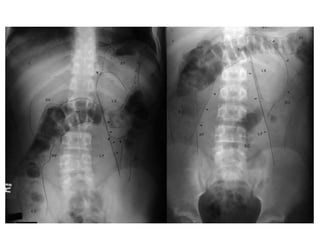

Rx Abdomen Normal

11va. Costilla

Cuerpo Vertebral.

Gas Estomacal.

Gas Colon Flexura Esplénica.

Gas Colon Transverso.

Gas Sigmoides.

Sacro.

Unión Sacro-Ilica.

Femur.

Gas en Ciego.

Cresta Iliaca.

Gas Colon Flexura Hepática.

Línea del Psoas.

Rx Abdomen Normal Supino 1. 2. 3. 4. 5. 6. 7. 8. 9. 10. 11. 12. 13. 11va.Costilla Cuerpo Vertebral. Gas Estomacal. Gas Colon Flexura Esplénica. Gas Colon Transverso. Gas Sigmoides. Sacro. Unión Sacro-Ilica. Femur. Gas en Ciego. Cresta Iliaca. Gas Colon Flexura Hepática. Línea del Psoas.